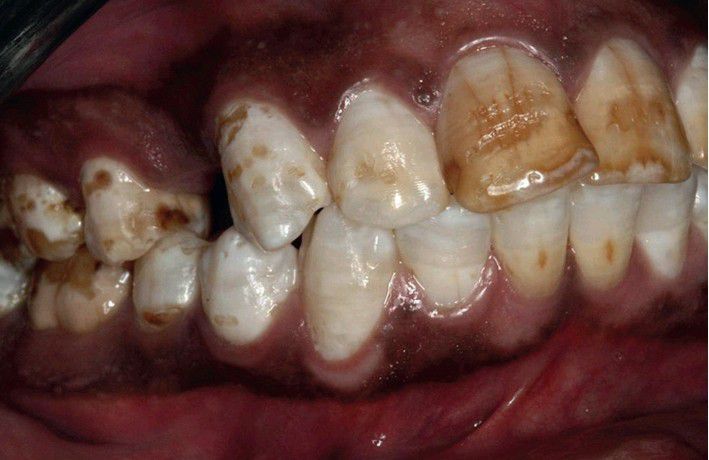

Flourosis

Diffuse white opaque alteration of the dentition with areas of brown enamel mottling. Patient spent his childhood in Keny